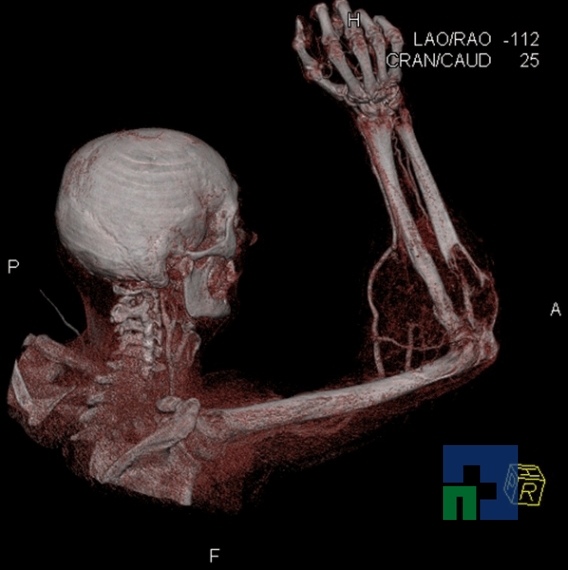

În cazul traumatismelor cranio-cerebrale:

- Evaluarea deplasării liniei mediane

- Evaluarea cisternelor perimezencefalice

- Diagnosticul edemului cerebral, a contuziei cerebrale, a leziunilor axonale difuze edematoase/hemoragice, a dilacerării cerebrale, a hematomului intraparenchimatos posttraumatic, a hematoamelor subdurale/extradurale (acute, subacute, cronice), a hemoragiei intraventriculare, a hemoragiei subarahnoidiene

- Diagnosticul traumatismelor de bază de craniu